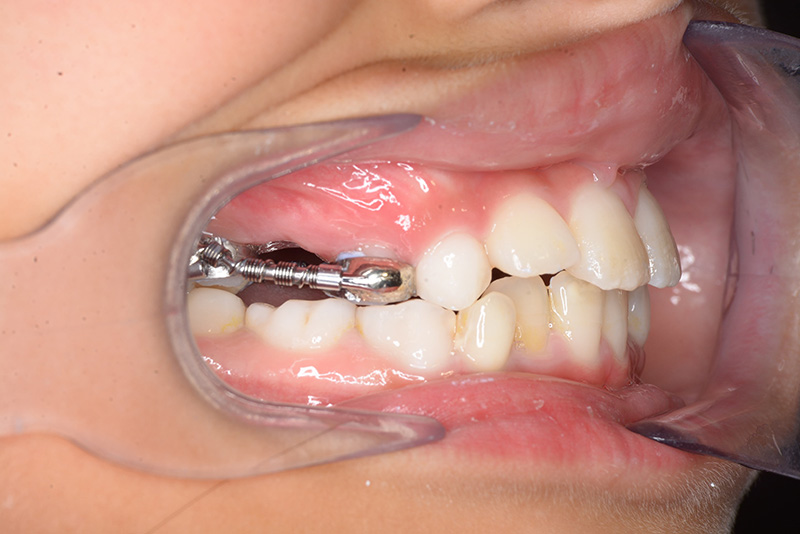

| 口腔内所見 | over jet 2.5mm、over bite 2.0mm、右側大臼歯関係はEnd on class Ⅱ、上顎左側Eは早期喪失により左側大臼歯関係はFull classⅡ、右側Eは6の異所萌出により歯根吸収が進行したため一般歯科医院にて抜去済みであった。 |

| パノラマ所見 | 上顎両側6、特に左側6は近心傾斜が認められ、両側5の萌出スペース不足が認められた。 |